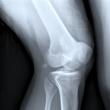

Nail patella syndrome

Nail patella syndrome (NPS), also called Fong's disease, hereditary onycho-osteodysplasia (HOOD), and Turner-Kieser syndrome, is a genetic disorder that causes physical abnormalities of the bones, joints, fingernails, kidneys, and eyes. It is generally... read more